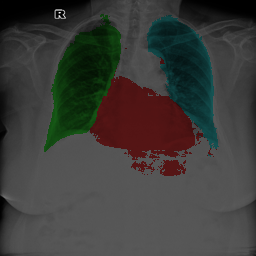

To bridge the methodological gaps when only small-scale partially labeled data is available, we propose a simple yet efficient framework Vicinal Labels Under Uncertainty (VLUU) by exploring the statistical similarity of human structures (e.g. shape, size, location) among different patients. See Fig. 1 for an illustration of such a similarity. The proposed framework is motivated by vicinal risk minimization (VRM) [11], where the fully labeled vicinal examples are generated by linearly combining randomly sampled partial labels with a weight randomly sampled from a Dirichlet distribution. These vicinal examples allow us to transform the partially supervised problem into a fully supervised one. That is to say, we can utilize any existing supervised segmentation networks and loss functions to solve partially supervised problems. The generated vicinal labels contain uncertainty regions where classes of interest could potentially overlap. We utilize these uncertainties in the training process to improve the robustness of DL models.

In standard adversarial training, the segmentation network and the discriminator play a zero-sum game. The discriminator is trained to discriminate the prediction masks produced by the segmentation network from the ground truth masks. Meanwhile, the segmentation network is trained to confuse the discriminator by producing realistic prediction masks. Adversarial training benefits from the human structure similarity as it makes the unknown true label distributions easier to be caught by the discriminator than for general objects [38]. In other words, there is smaller instance-wise variation in the size, shape, and location of human organs (or structures), as shown in Fig. 1, than for general objects.